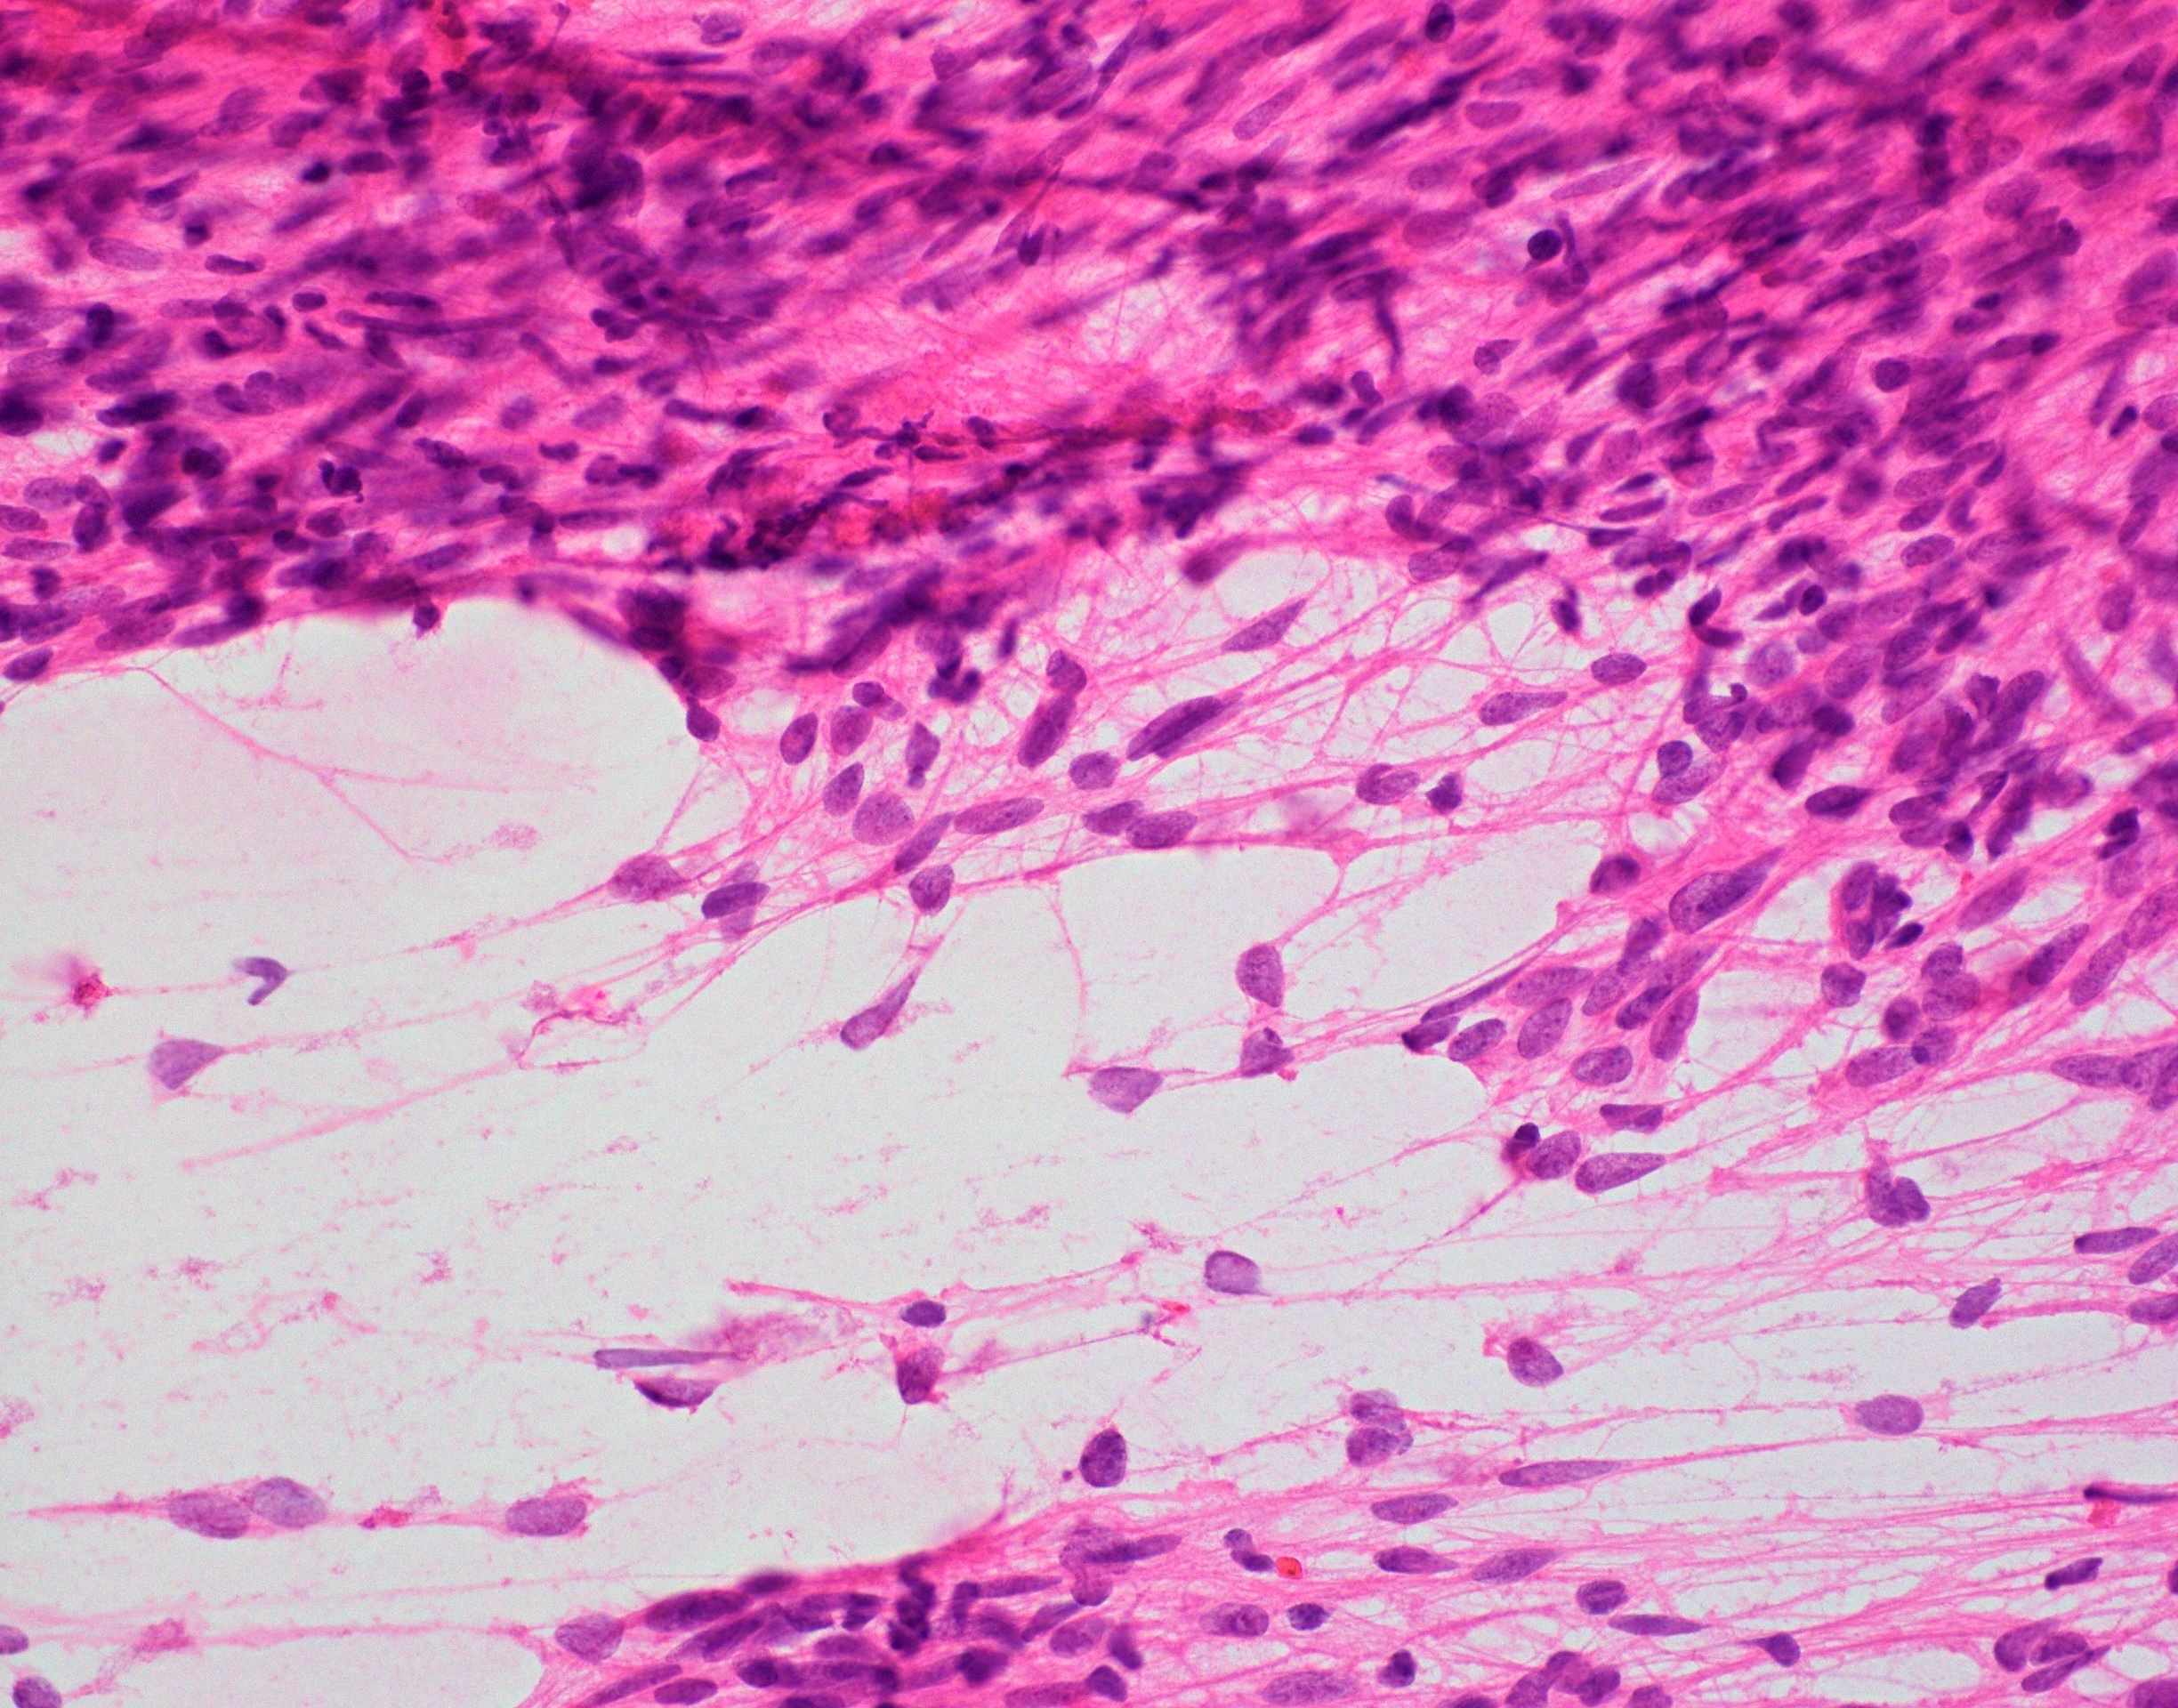

Microscopic (histologic) description

- Cellular tumor with typically sharply circumscribed borders; may be infiltrative

- Perivascular pseudorosettes, true ependymal rosettes, lumina and fibrillar areas

- Morphologic subtypes have no clinicopathological significance and include papillary, clear cell and tanycytic

Microscopic (histologic) images